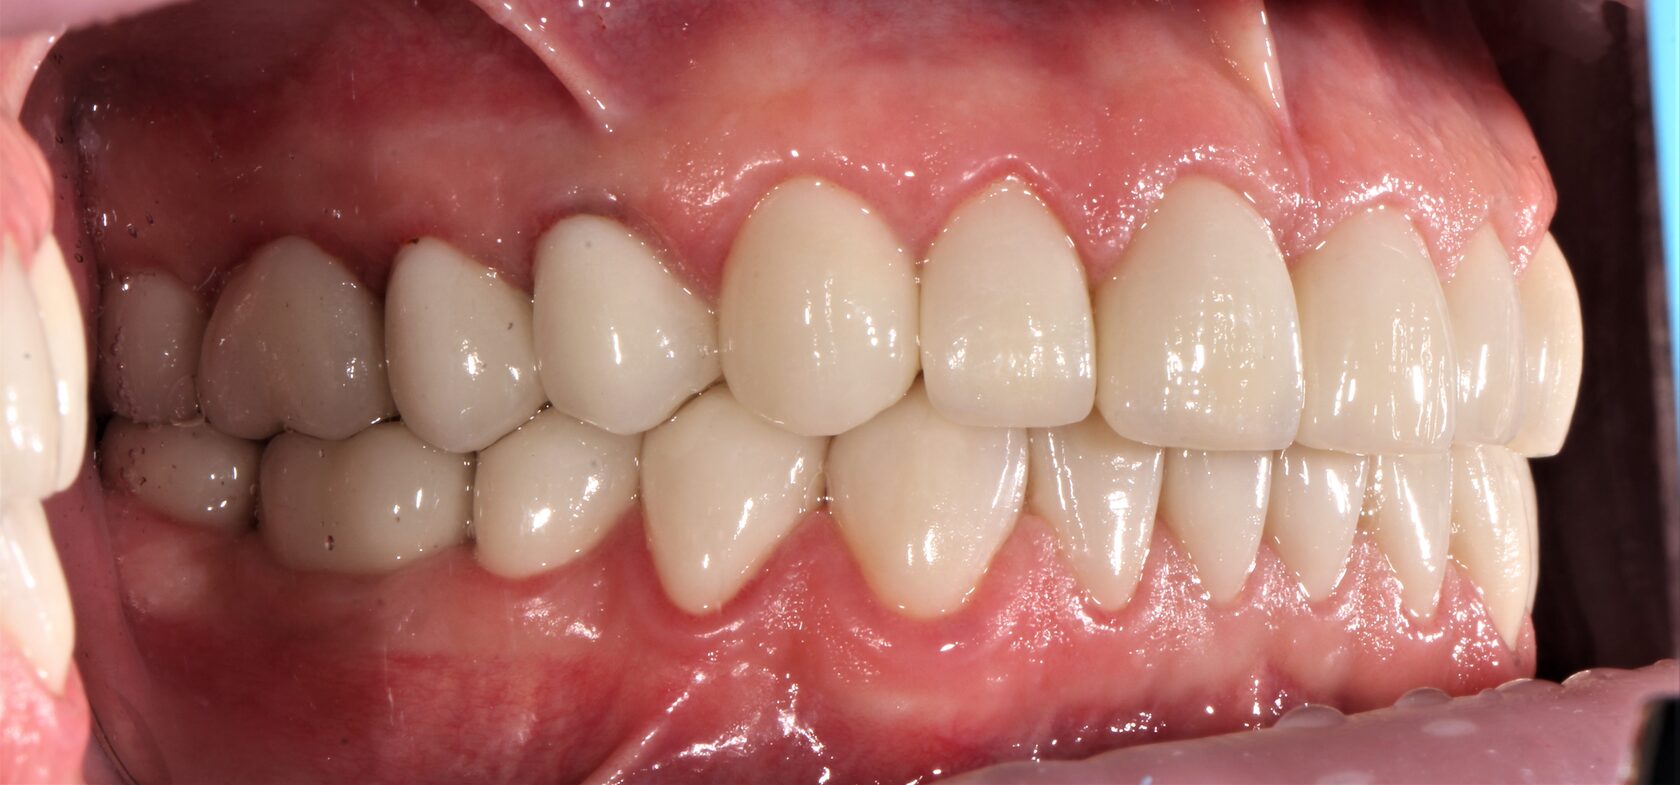

В данном клиническом случае представлена комплексная работа, состоящая из:

1 Терапевтический этап - лечение кариеса, подготовка корневых каналов и восстановление

культей зубов для установки коронок.

2 Хирургчий этап - удаление 2-х зубов с одномоментной дентальной имплантацией.

3 Сложное функционально-эстетическое протезирование (завышение прикуса на временных

коронках, стабилизация мышечного тонуса и позиции ВНЧС, перевод временных конструкций

в постоянные).

Длительность лечения составила более 1 год.